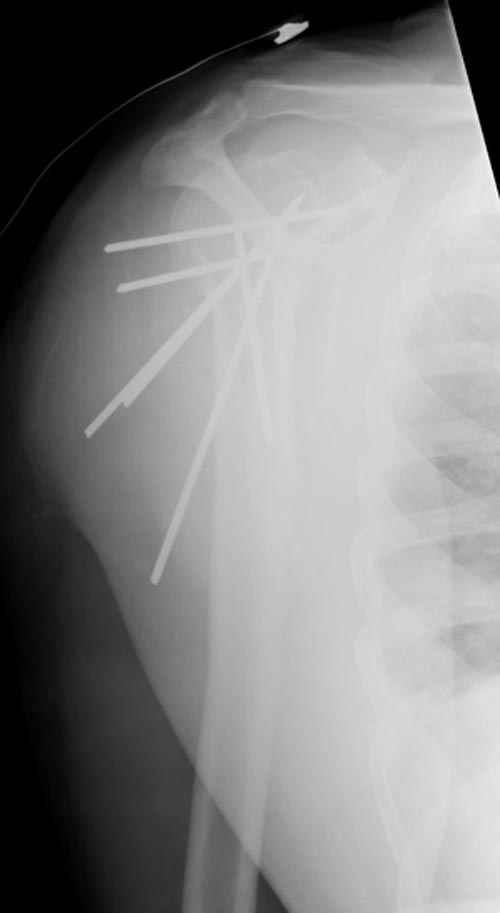

Здесь случай перелома-вывиха плеча, больному 56 лет, после "дважды" закрытой неудачной репозиции, опять же ургентно взяли в операционную, после полного общего обезболивания попытались сделать репозицию, и фиксацию провели спицами.

Больной находился в повязке, примерно напоминяющей косыночную, рекомендованы движения в локтевом суставе и маятниковые движения в плече, спицы удалены в три недели (были случаи миграции)

Больной амбулаторный, предупрежден на случай осложнения АВН головки.

Клинические снимки - 3 недели после операции